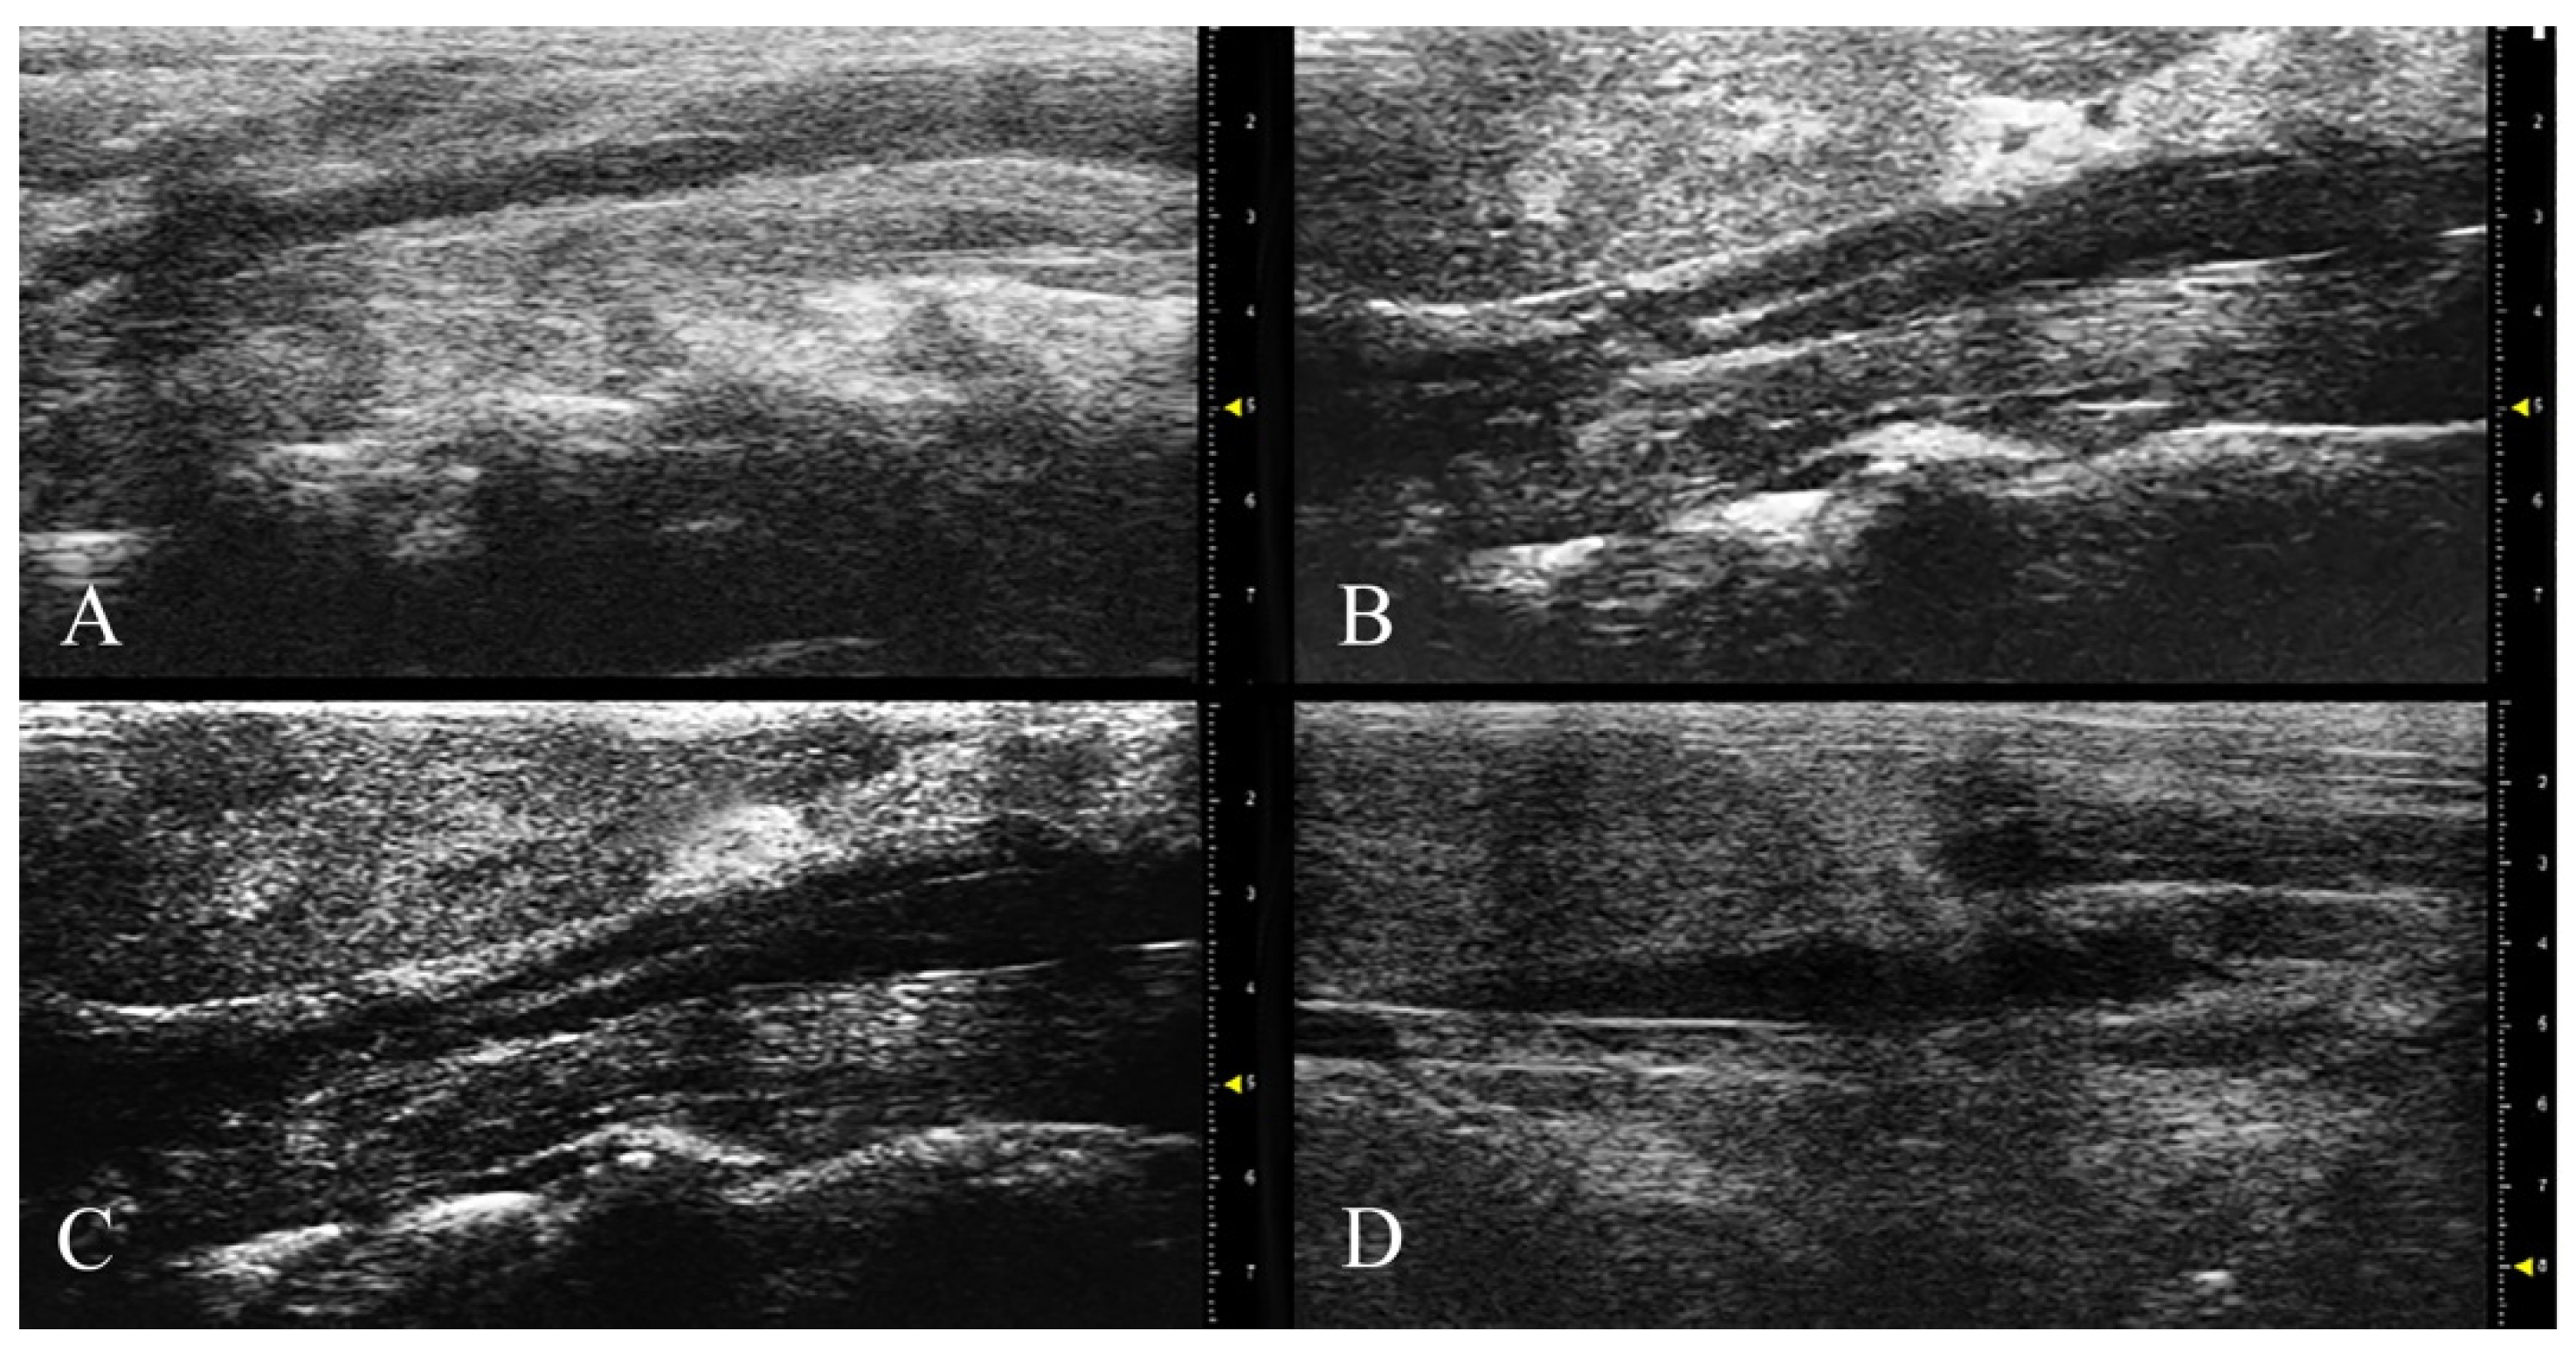

2.3. Abdominal High-Frequency Ultrasound

3.2. HFUS and MRI Monitoring